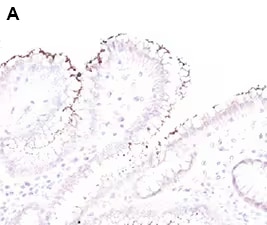

Immunohistochemistry analysis of Helicobacter pylori expression in human stomach tissue

Immunohistochemical analysis of Helicobacter pylori in Formalin-fixed paraffin-embedded human stomach tissue sections with a rabbit polyclonal antibody to Helicobacter pylori lysate, Helicobacter pylori Antibody [NBP2-29479]